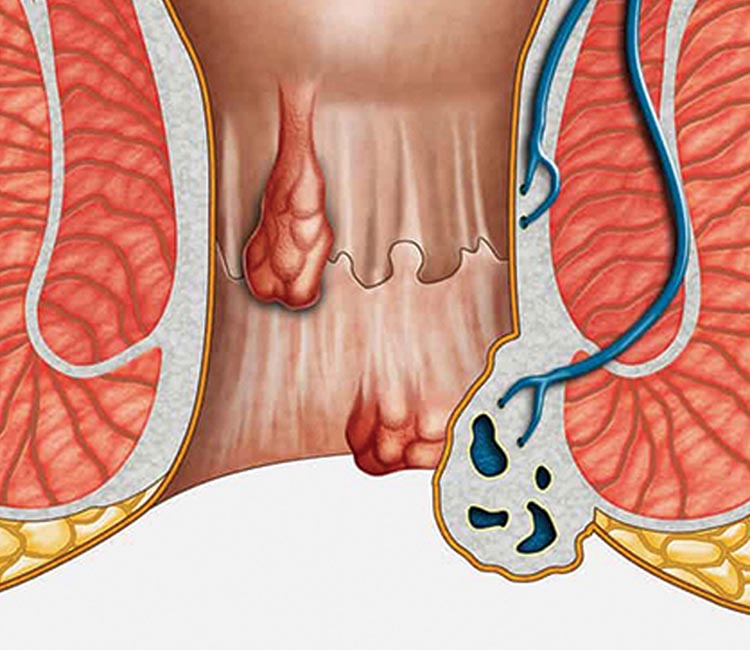

We specialize in advanced hemorrhoid treatments, using the latest surgical techniques for effective relief from discomfort, pain, and bleeding, ensuring a faster recovery with minimal downtime.